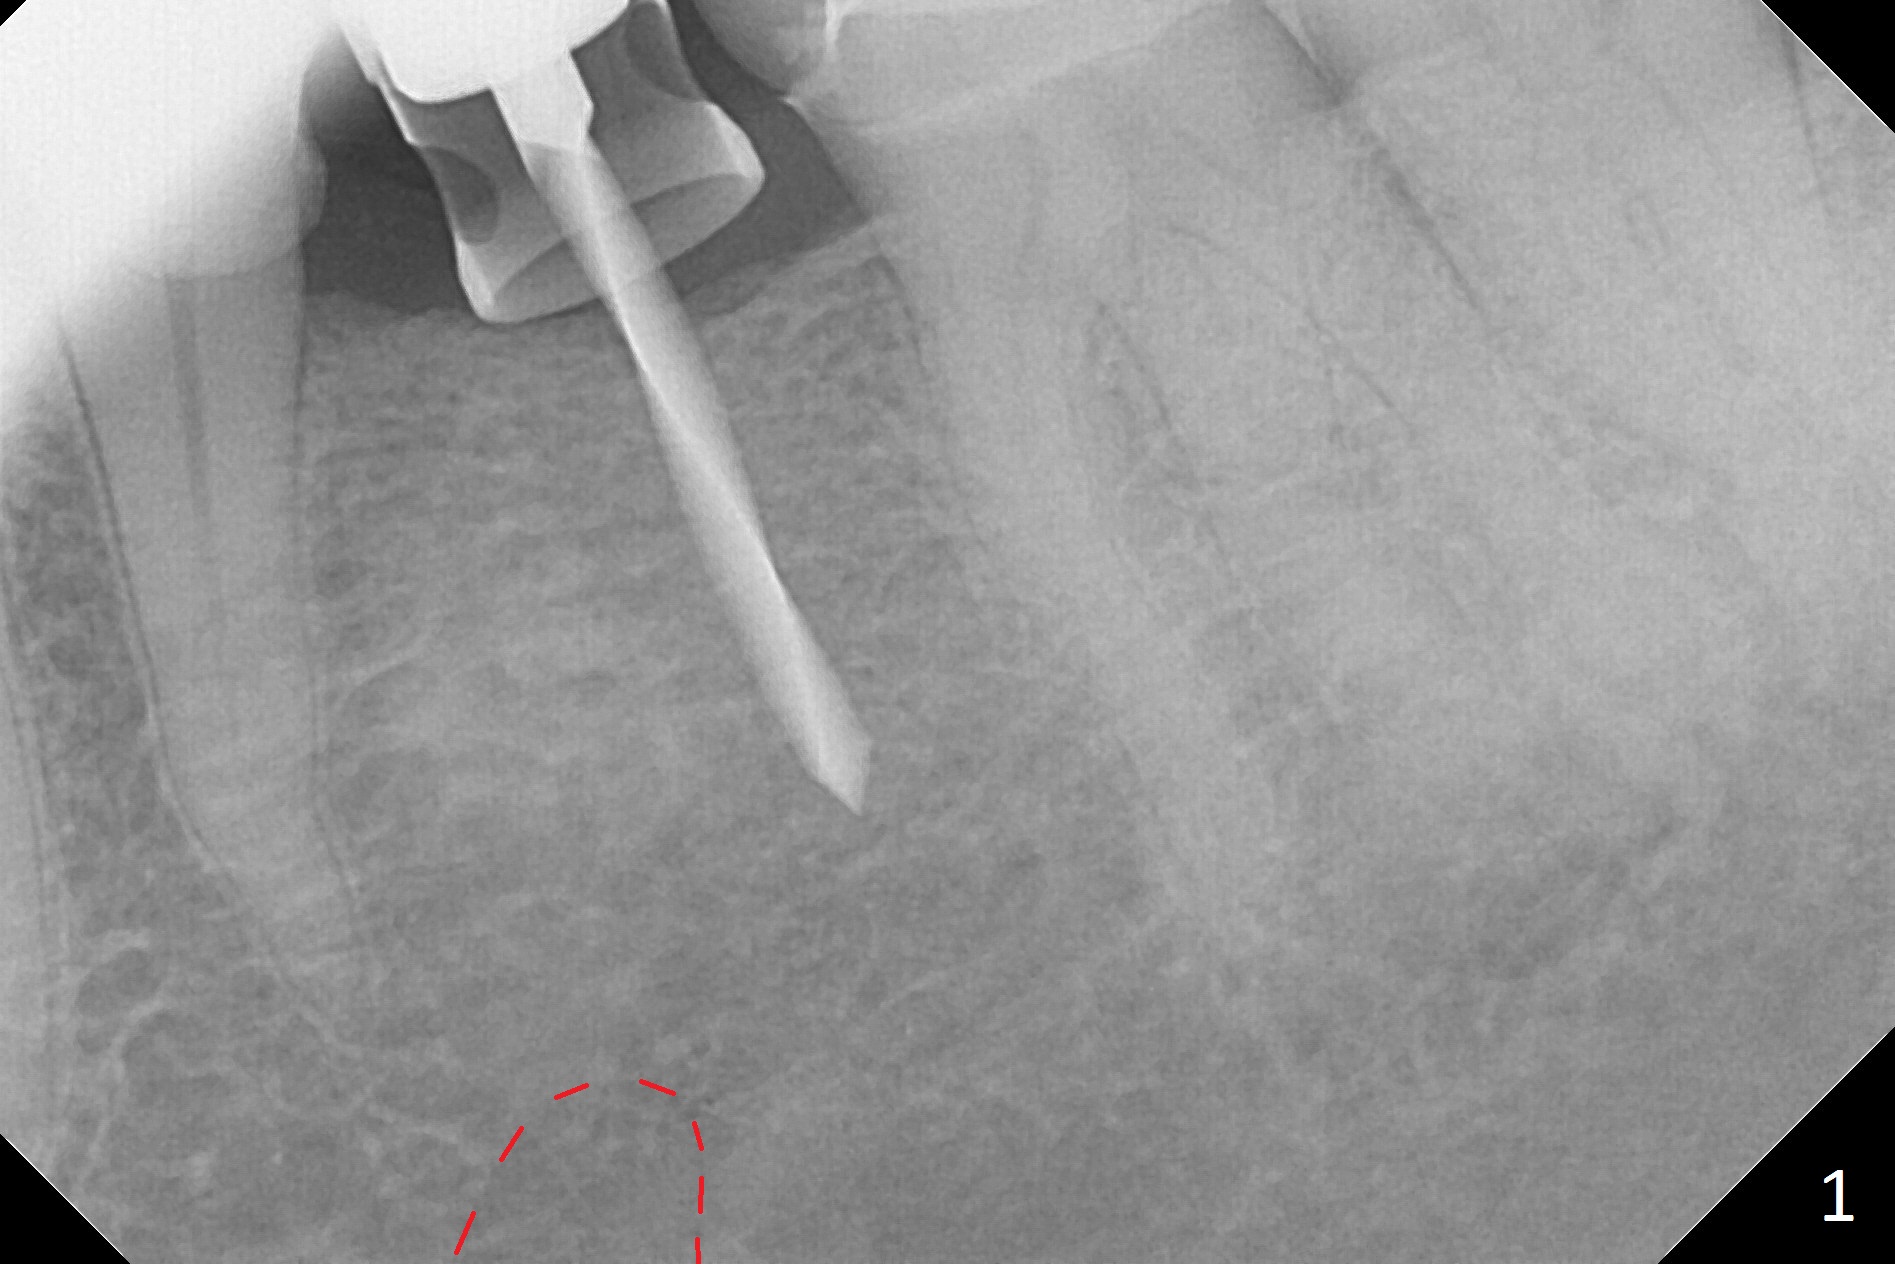

Initial osteotomy with 1.6 mm drill for 11 mm seems to be distal (Fig.1). The trajectory should be changed as shown by the black line in Fig.2; the drawback would be close to the Mental Loop (red line). Fortunately the trajectory is changed, but not so much as to be close the Loop when a 4x11 mm dummy implant is placed (Fig.3). When a 4x13 mm IBS is placed with 46 Ncm, there is clearance from the Loop (Fig.4-6). In fact there is no postop paresthesia. The main point is no block anesthesia. Infiltration anesthesia is administered with 34 mg Xylocaine with 17 mcg Epinephrine. The patient experiences dull pain when the implant is placed (Fig.4-6). After further anesthesia with 68 mg Septocaine, 17 mcg Epinephrine, the implant is torqued for a few turns (still with some discomfort). Finally autogenous bone with Osteogen is placed around the implant following placement of a 4.5x4(2) mm abutment. To reduce anxiety, a shorter implant should have been used. The patient complains of cold sensitivity in the lower left quadrant 4 months postop (Fig.7): the implant apparently close to the Mental Loop. Without an immediate provisional, the gingiva around the abutment is healthy.